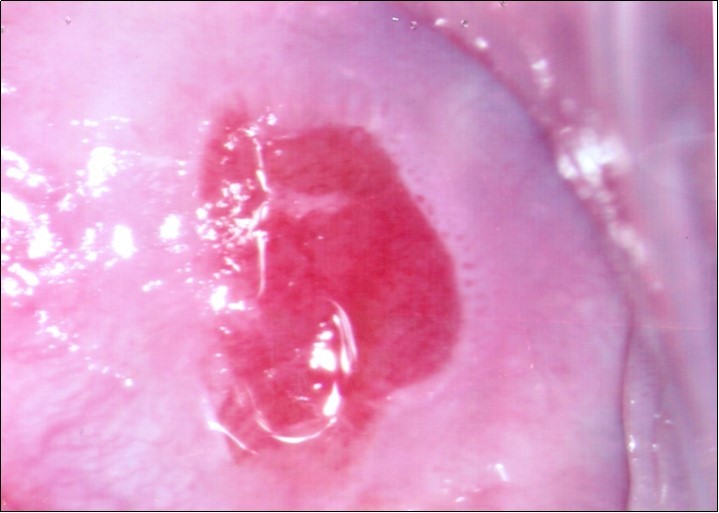

Repeat colposcopy was performed after 6 weeks. This revealed a small ulcerated area at the site of previous biopsy with rolled healing edges, and a separate small ulcer at the 12 o’clock position. (Figure 2a, Figure 2b, Figure 2c) Careful inspection of the buccal mucosa revealed similar ulcers in the left buccal region. (Figure 3)

Figure 2c.Repeat colposcopy (high magnification)